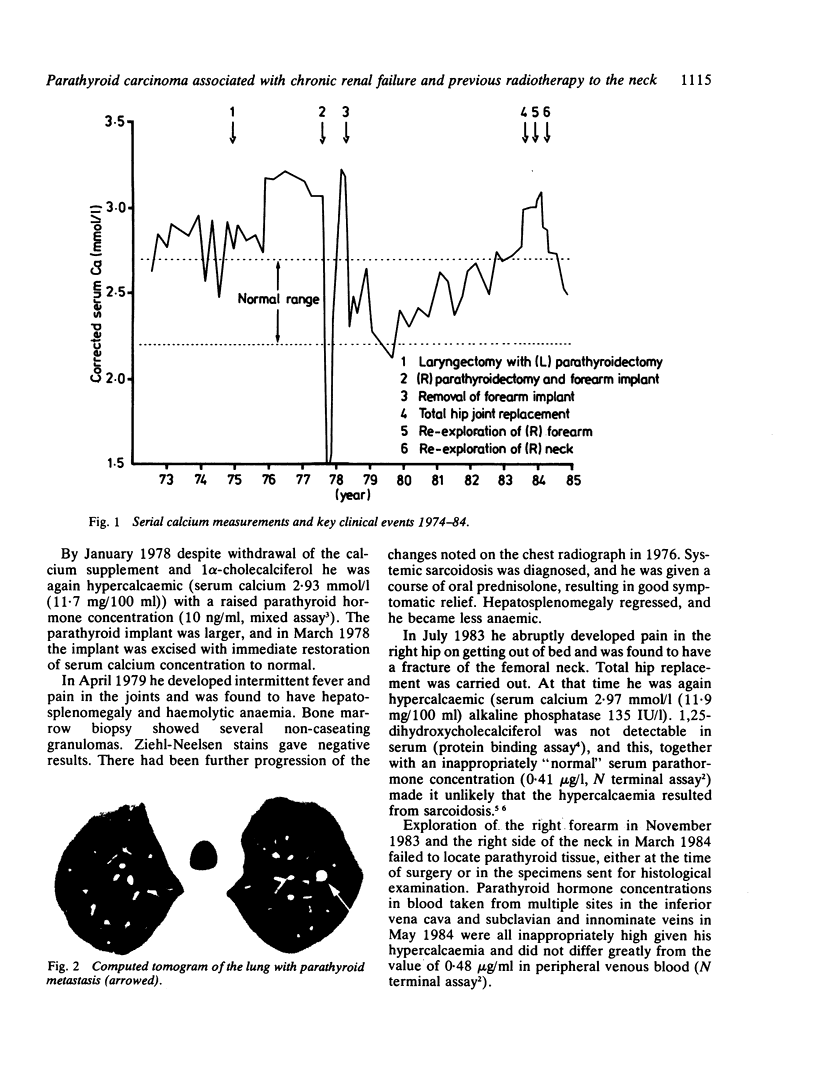

Carcinoma of the larynx was treated by irradiation followed by laryngectomy in a man who had been receiving regular haemodialysis for two years. At least one, and probably two, parathyroid glands were removed at this time, and the remaining two were removed three years later for tertiary hyperparathyroidism. A portion of one gland was implanted into the forearm. The forearm implant was resected the following year for recurrent hypercalcaemia. Six years later, again with recurrent hypercalcaemia, he died of bronchopneumonia. Metastatic parathyroid carcinoma was found in the apex of the left lung. The source of this parathyroid tissue and the possible role of irradiation in the pathogenesis of parathyroid cancer in this patient were investigated.